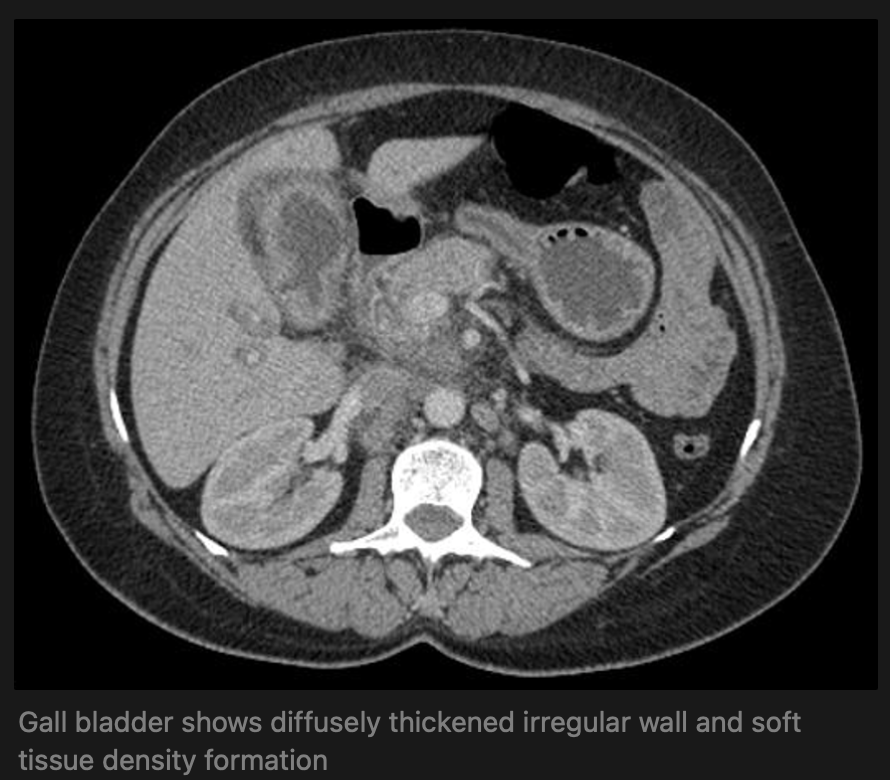

Radiological presentation: one of three morphologies:

• Intraluminal mass

• Diffuse mural thickening

• Mass replacing the gallbladder, most common presentation

• presumably the end result of progression from either 1 or 2

CT Scan - appear as large heterogeneous masses, which may have engulfed gallstones or areas of necrosis, patchy moderate contrast enhancement is usually seen.

Features of advanced disease include:

• intrahepaticbiliary dilatation

• invasion of adjacent structures

• lymphadenopathy

• peritoneal carcinomatosis

• hepatic and other distant metastases